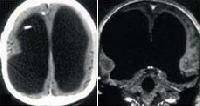

Магнитно-резонансная томография (МРТ):один из самых эффективных методов диагностики заболеваний